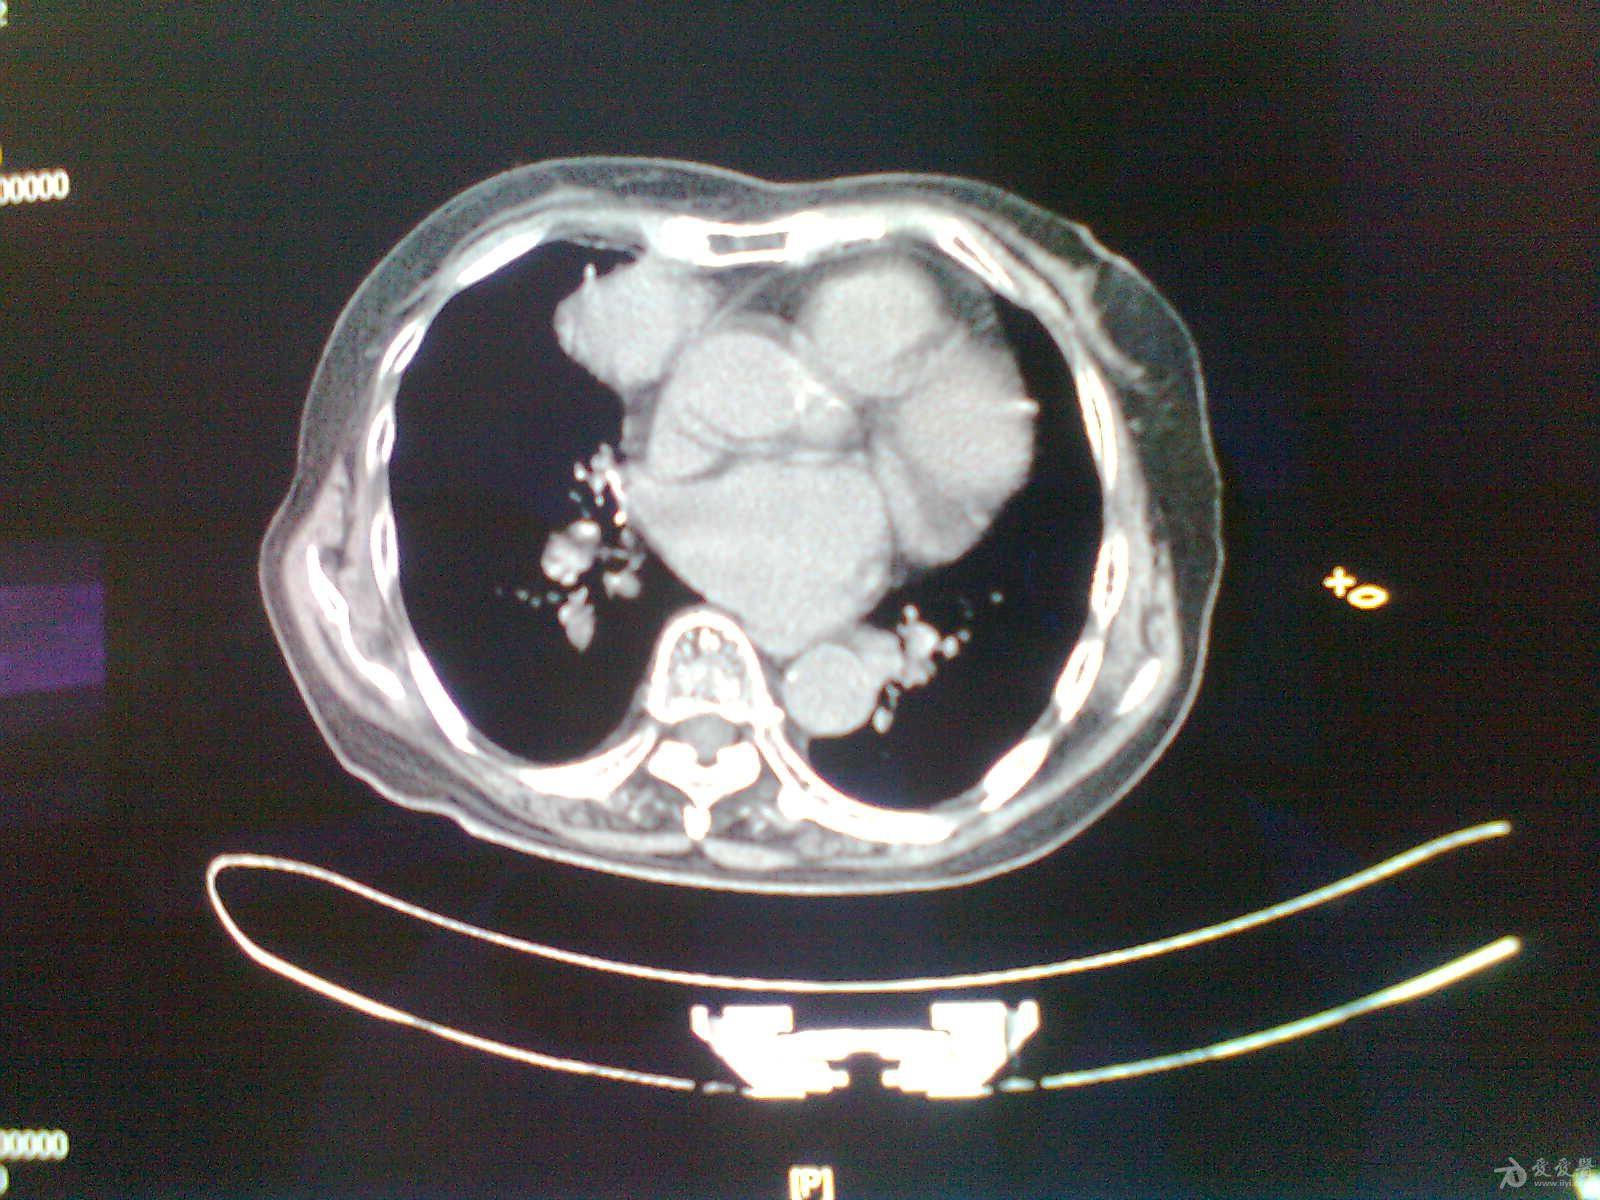

楼主artest2013-11-24 11:33:10男 62岁,右心膈角占位性病变 ct值约

男62岁,右心膈角占位性病变

右肺心膈角处囊性病变.请各位老师看看.